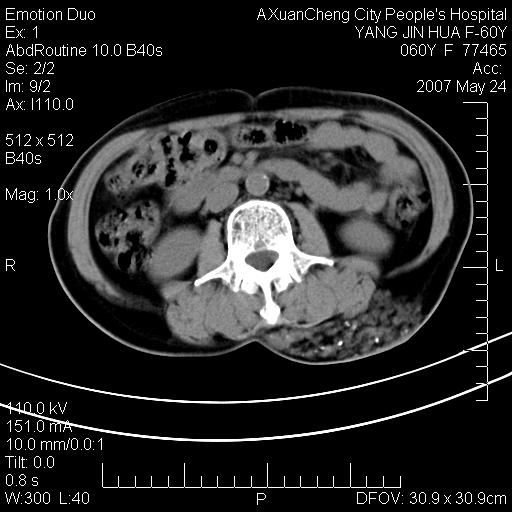

发现左侧腰背部包块40余年,逐渐长大,质软,局部表面可见扩张的血管影

左背部皮下良性肿瘤,密度不均,边界不清,内有脂肪、钙化,增强扫描无明显强化,血管平滑肌脂肪瘤?进一步诊断有困难,建议穿刺活检。

左侧背部皮下混杂密度肿块,结构较疏松,边缘欠光整,内有多发斑点状钙化,考虑:皮下血管瘤。

其内可见斑点状静脉石,血管瘤有时就不增强化,还是血管瘤。

1、病灶内有小点状钙化,静脉石?这可是血管瘤诊断的重要征象

2、病灶内有脂肪组织增生,血管瘤有此特点

还是考虑皮下血管瘤,强化不明显可能跟大量血栓形成有关,好多战友考虑血管平滑肌脂肪瘤,血管平滑肌脂肪瘤的血管就不强化么?只要有血管就都应该强化。